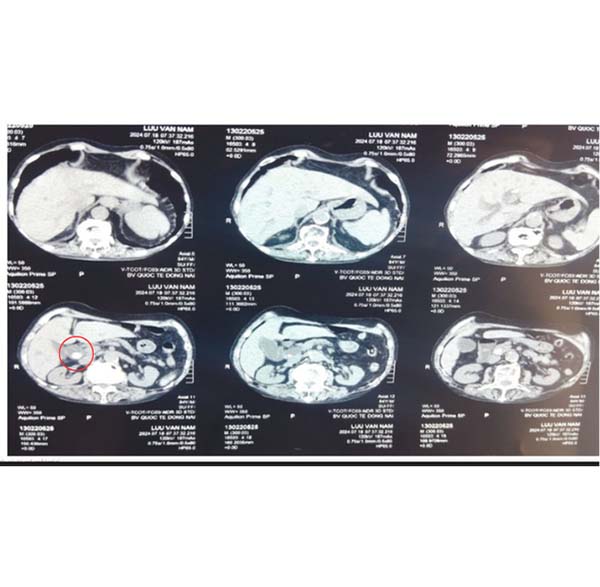

Sau đó, bệnh nhân được chụp CT scan bụng, phát hiện sỏi khoảng 15mm ở đoạn cuối ống mật chủ, sỏi ở ống gan chung và nhánh trái của gan khoảng 12mm. đường mật trong và ngoài gan giãn, ít sỏi bùn túi mật. Xét nghiệm máu có Bilirubin toàn phần và trực tiếp tăng chiếm ưu thế.

Sỏi đường mật nhánh gan trái. Ảnh: Bệnh viện cung cấp